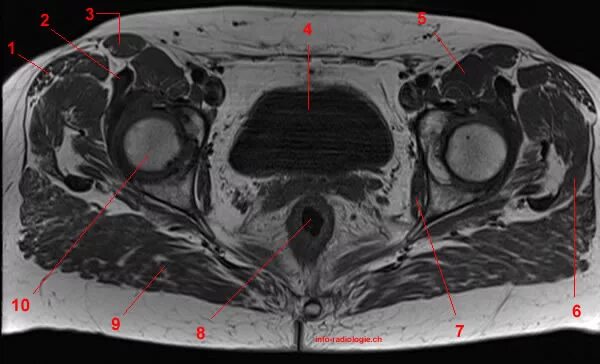

Мрт большого таза